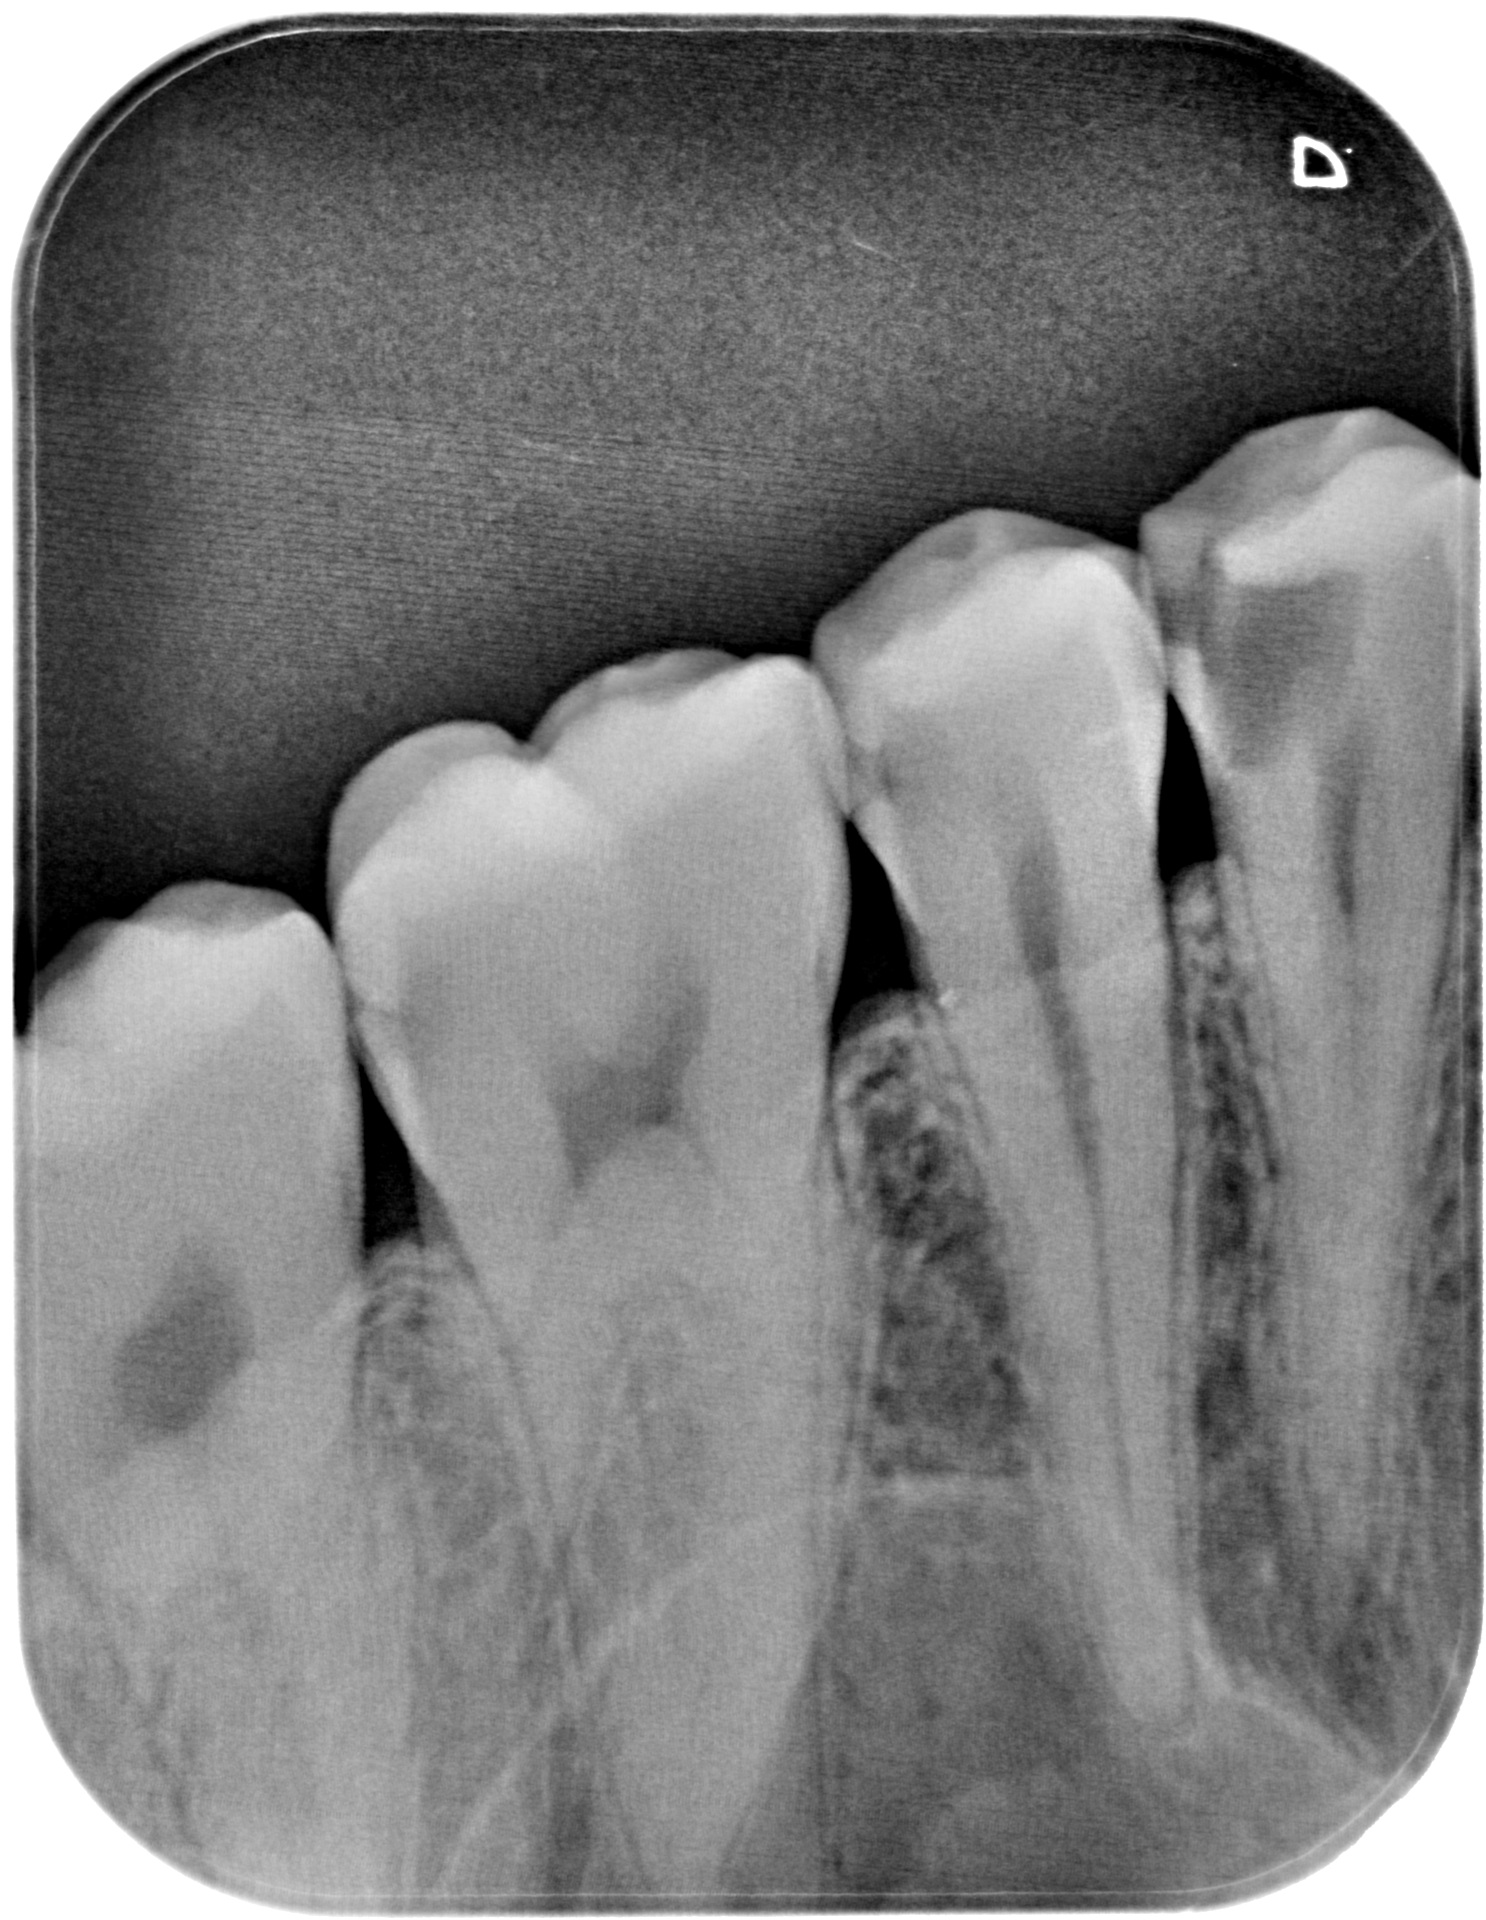

We use rotary nickel-titanium instruments, activated irrigation for deep disinfection, and modern bioceramic sealers for a dense, long-lasting seal. - Targeted diagnostics

- Clinical assessment and plan

We examine the tooth, test its response, and take focused images. When roots are complex or a previous treatment failed, a small 3D scan may be needed for mapping before we discuss and agree on the plan. - Anaesthesia and comfort

Under bright magnified light, a tiny opening is created and every canal located — even the hidden ones that often cause failures elsewhere. - Cleaning and shaping